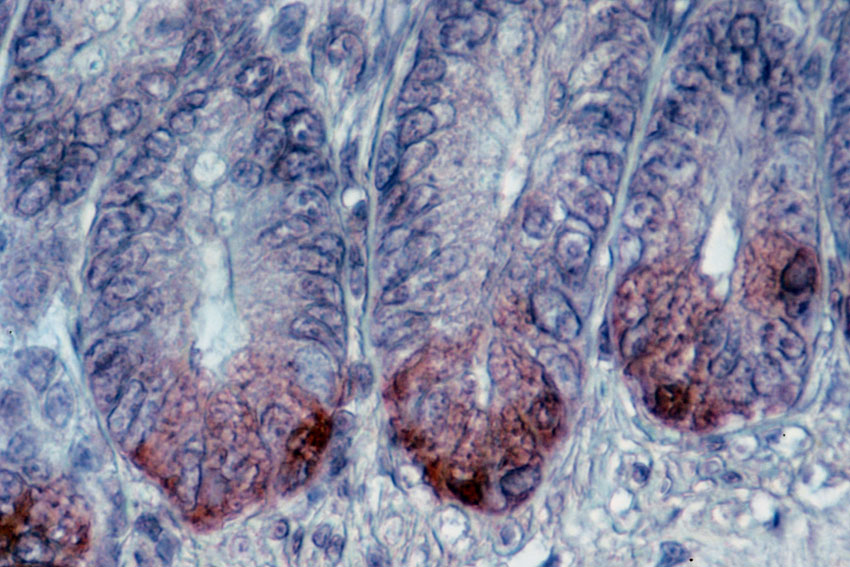

| Carcinome du pancréas. Source: http://www.inserm.fr/thematiques/cancer/dossiers/cancer-du-pancreas |